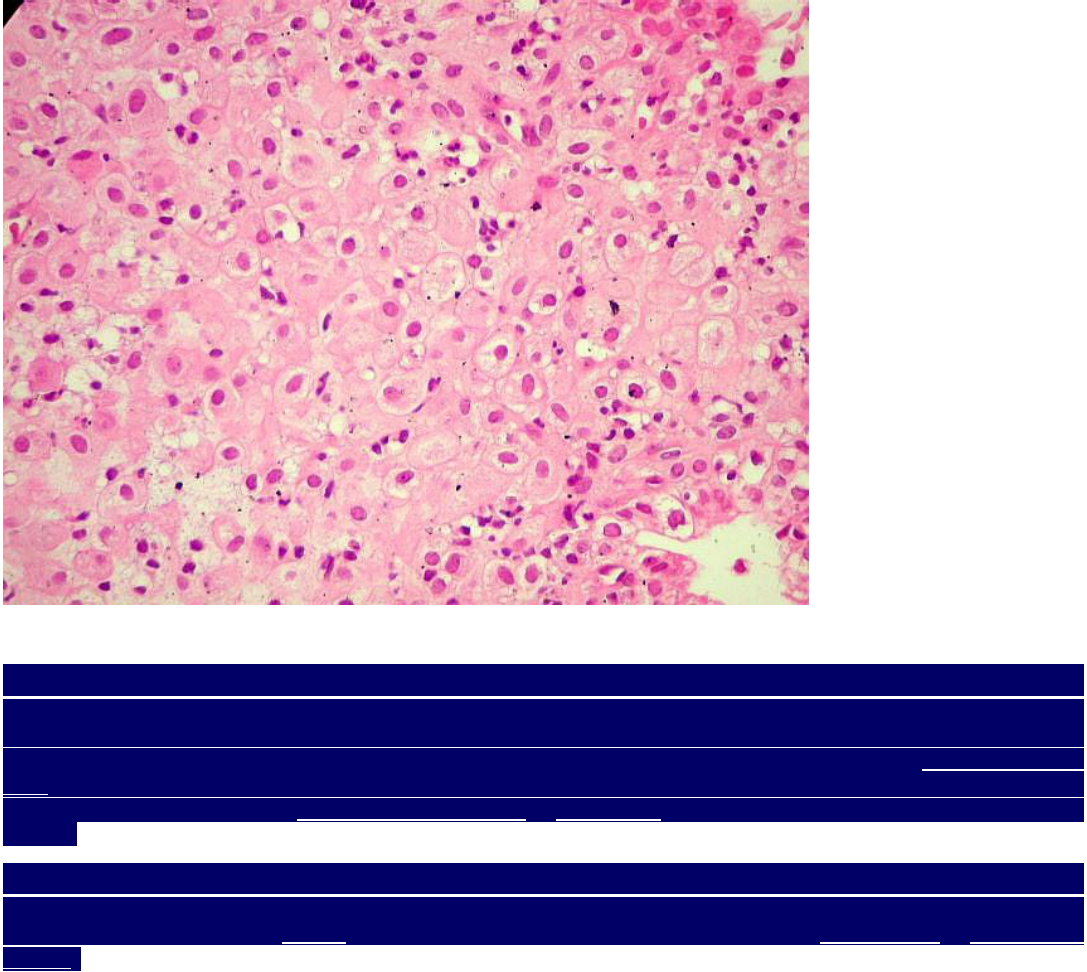

GLÂNDULAS  ENDOMETRIAIS  EM  FASE  SECRETÓRIA.  Este raspado de endométrio provém de um aborto, e mostra acentuada ação progesterônica, uma vez que, na gravidez, os níveis de progesterona são altos. As  glândulas assumem disposição sinuosa dando à luz contorno estrelado. As células glandulares têm citoplasma amplo, róseo e às vezes vacuolado, devido à abundante secreção.    Em muitas, observa-se hipercromatismo nuclear, por vezes acentuado, o que constitui o  fenômeno de Arias-Stella, próprio da gravidez. Este é atribuído a poliploidia das células pelo estímulo progesterônico. As células fazem proeminência na luz da glândula e são chamadas de células em cabeça de prego ou hobnail cells.  Não são observadas mitoses, nas glândulas ou no estroma.

ESTROMA  ENDOMETRIAL  GRAVÍDICO.   Na gravidez, as células do estroma endometrial sob ação progesterônica  mostram-se volumosas, com citoplasma abundante róseo, e podem assumir contorno arredondado.  O endométrio gravídico é também chamado de decídua, e a modificação das células estromais é referida como decidualização ou transformação decidual.